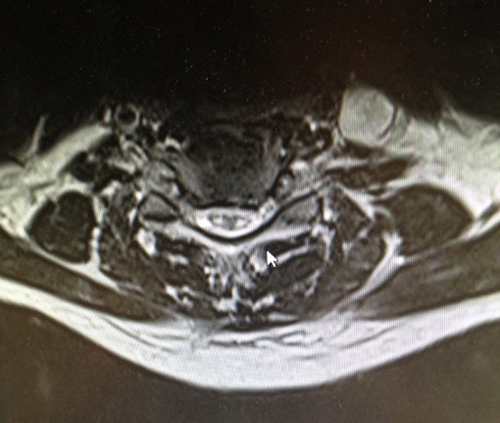

À l’examen clinique : la patiente est désorientée. Elle a une amputation dans les hémichamps visuels gauches des deux yeux. Le testing moteur vous semble légèrement plus faible aux deux membres inférieurs, vous ne parvenez pas à évaluer la sensibilité. Ses réflexes ostéo-tendineux sont vifs aux membres inférieurs, vous retrouvez une extension lente des deux hallux lorsque vous effleurez la plante des pieds avec votre marteau. Lorsque vous regardez les chaussures de la patiente, il vous semble que l’avant de ses chaussures est très abîmé par rapport à l’arrière.